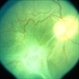

- toxocara granuloma

- Fundus photo showed central posterior granuloma on the optic nerve